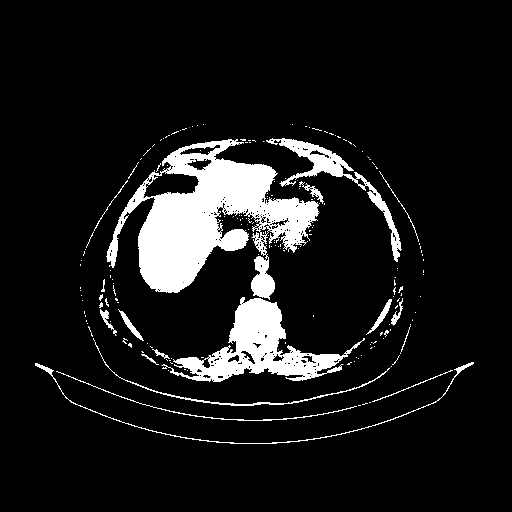

Original VENOUS CT scan

Full window (WL 1023.5, WW 4095 β†’ Low βˆ’1024, High +3071)

Actual HU range: [-1024.0, 3071.0]